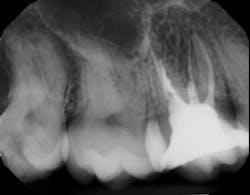

There is sufficient bone support around the remaining roots (at least 50% or more is needed) along with sufficient coronal tooth structure (figure 3).How does root amputation compare with other surgical procedures?